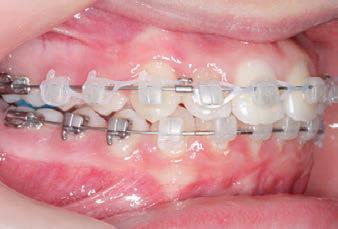

CLASS II DIV.1 - Marra

PROGRESS 3 - 30/10/18 - With M-TWO .020 x .020 Cu Nitanium 35° archwire

PROGRESS 4 - 27/11/18 - 3 links power chain: 5, 4, bypass 3 to crimp hooks

PROGRESS 5 - 13/3/19 - With M-TWO .020 x .020 Cu Nitanium 35° archwire

PROGRESS 6 - 1/8/19 - With M-THREE.019 x .025 Beta Titanium wire